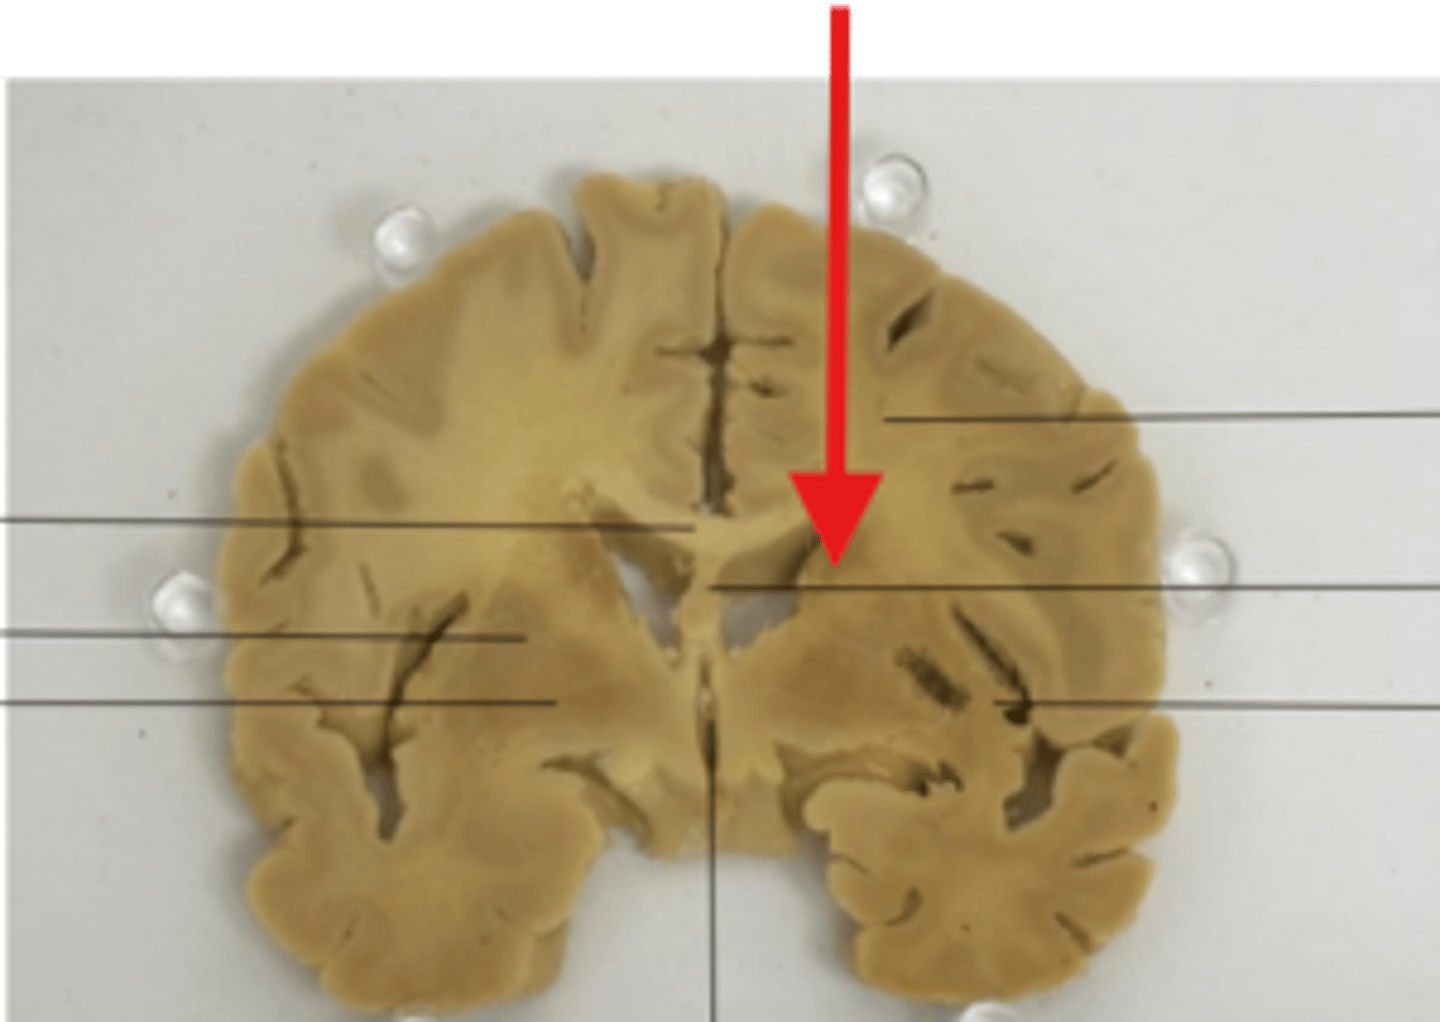

What is the red arrow pointing at?

what structure is the red arrow pointing at?